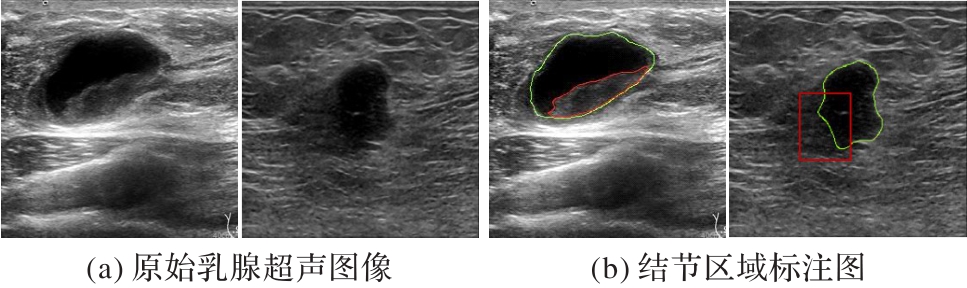

大连大学. 基于多尺度和跨空间融合的超声乳腺结节端到端分割方法: 202211177184.X[P]. 2023-01-06.

Dalian University. End-to-end segmentation of ultrasound breast nodules based on multi-scale and cross-spatial fusion: 202211177184.X[P]. 2023-01-06.